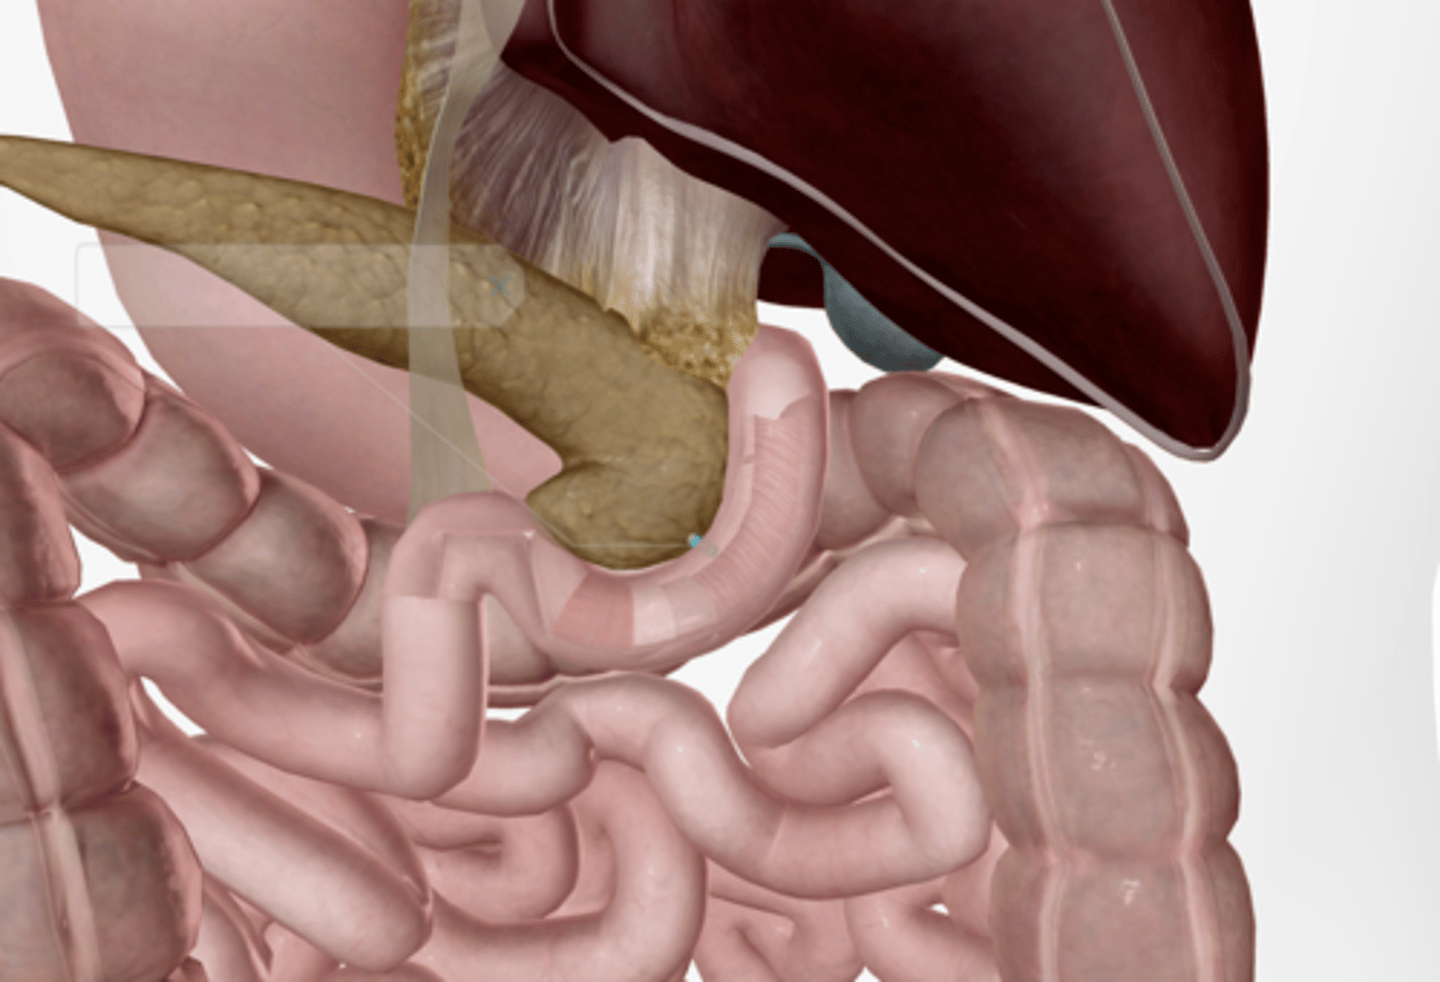

Gallbladder

Cystic duct

Common hepatic duct

Common bile duct

Pancreas

Main pancreatic duct (duct of Wirsung)

Accessory pancreatic duct (duct of Santorini)

Liver

Duodenum

Duodenal papilla